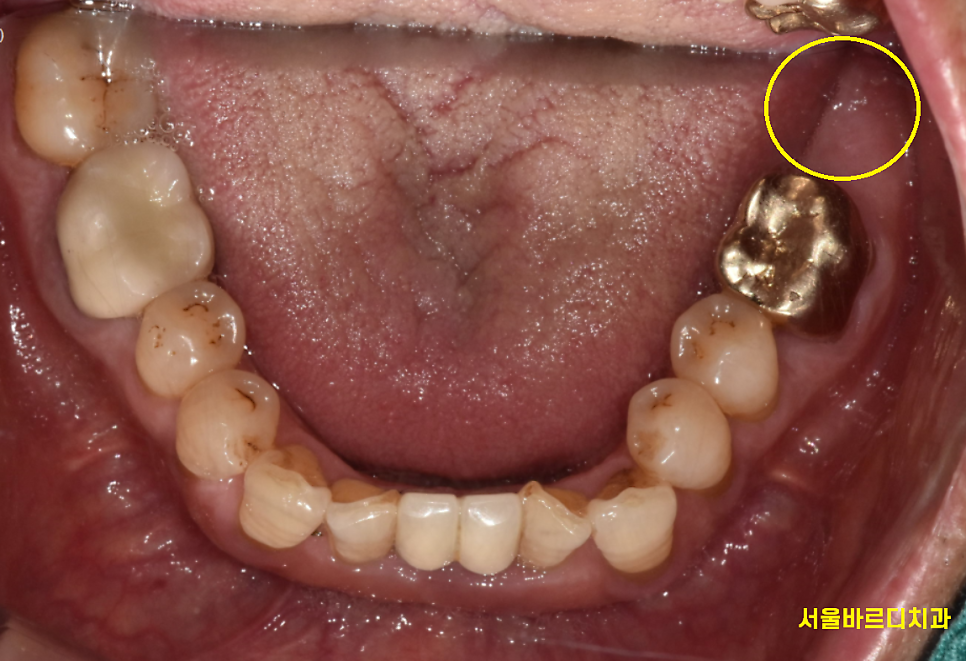

없었던 큰 어금니 1개

보험 임플란트 덕분에 회복했습니다.

크기가 큰 놈이 두개나 더 생겼으니

오른쪽, 왼쪽 대칭감있게

이제 식사하시면 되겠네요~

늘 강조드리고 싶은 말씀은

양쪽 균형이 중요하다는 얘기입니다.